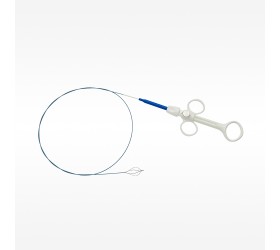

Ampla oferta de cateteres para tratamento de acesso arterial, venoso e AV em vasos variando de 1,5 mm a grandes vasos iliofemorais

Especificações de Cateter

| Modelo | Indicação | Plataforma de Liberação | Diâmetro Mínimo do Vaso | Comprimento do Cateter | Diâmetro do Cateter | Fio-guia | Power Pulse™ Habilitado | Fio-Guia Alternável | Porta de Injeção de Contraste |

|---|---|---|---|---|---|---|---|---|---|

| ZelanteDVT™ | Venoso | OTW | 6 mm | 105 cm | 8 F | 0,035” | Sim | Sim | Sim |

| Solent™ Omni | Acesso AV, Arterial e Venoso Periférico | OTW | 3 mm | 120 cm | 6 F | 0,035” | Sim | Sim | Sim |

| Solent™ Proxi | Acesso AV, Arterial e Venoso Periférico | OTW | 3 mm | 90 cm | 6 F | 0,035” | Sim | Sim | Sim |

| Solent™ Dista | Arterial Periférico | OTW | 1,5 mm | 145 cm | 4 F / 3 F | 0,014” | Sim | N/A | N/A |

| AVX™ | Fístula e Enxertos de Acesso AV | OTW | 3 mm | 50 cm | 6 F | 0,035” | N/A | N/A | Sim |